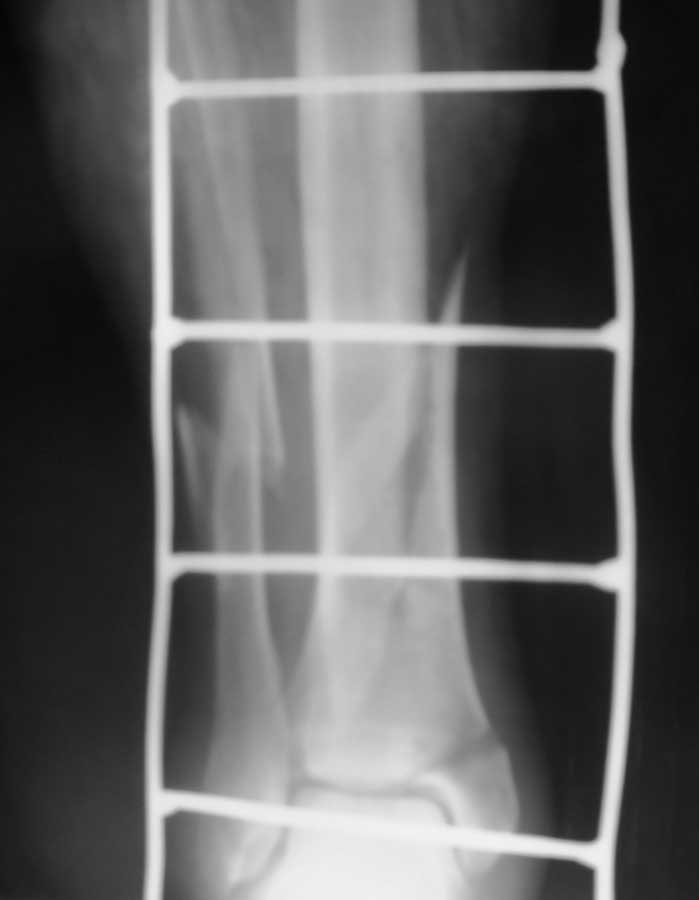

[Ortho] открытый перелом н/3 обеих костей левой глени

рентгенограммы

Вложение не в текстовом формате было извлечено…

Имя     : 100_0376[1].JPG

Тип     : image/jpg